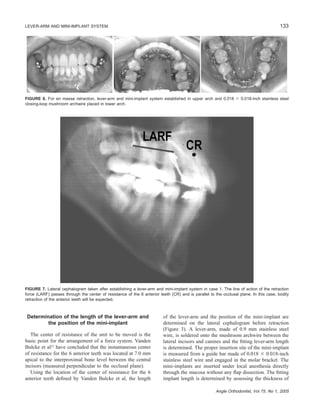

FIGURE 3. According to clinical situations, the length of the lever-arm and the position of the mini-implant are determined on the lateral

cephalogram. OP indicates occlusal plane; IPBL, interproximal bone level between the central incisors; CR, center of resistance of the 6

anterior teeth; LA, lever-arm; and GB, guide bar.

FIGURE 4. Intraoral photographs before (A) and after (B) establishing a lever-arm and mini-implant system.

Determination of the length of the lever-arm and

the position of the mini-implant

The center of resistance of the unit to be moved is the

basic point for the arrangement of a force system. Vanden

Bulcke et al23

have concluded that the instantaneous center

of resistance for the 6 anterior teeth was located at 7.0 mm

apical to the interproximal bone level between the central

incisors (measured perpendicular to the occlusal plane).

Using the location of the center of resistance for the 6

anterior teeth defined by Vanden Bulcke et al, the length

of the lever-arm and the position of the mini-implant are

determined on the lateral cephalogram before retraction

(Figure 3). A lever-arm, made of 0.9 mm stainless steel

wire, is soldered onto the mushroom archwire between the

lateral incisors and canines and the fitting lever-arm length

is determined. The proper insertion site of the mini-implant

is measured from a guide bar made of 0.018 ϫ 0.018-inch

stainless steel wire and engaged in the molar bracket. The

mini-implants are inserted under local anesthesia directly

through the mucosa without any flap dissection. The fitting

implant length is determined by assessing the thickness of